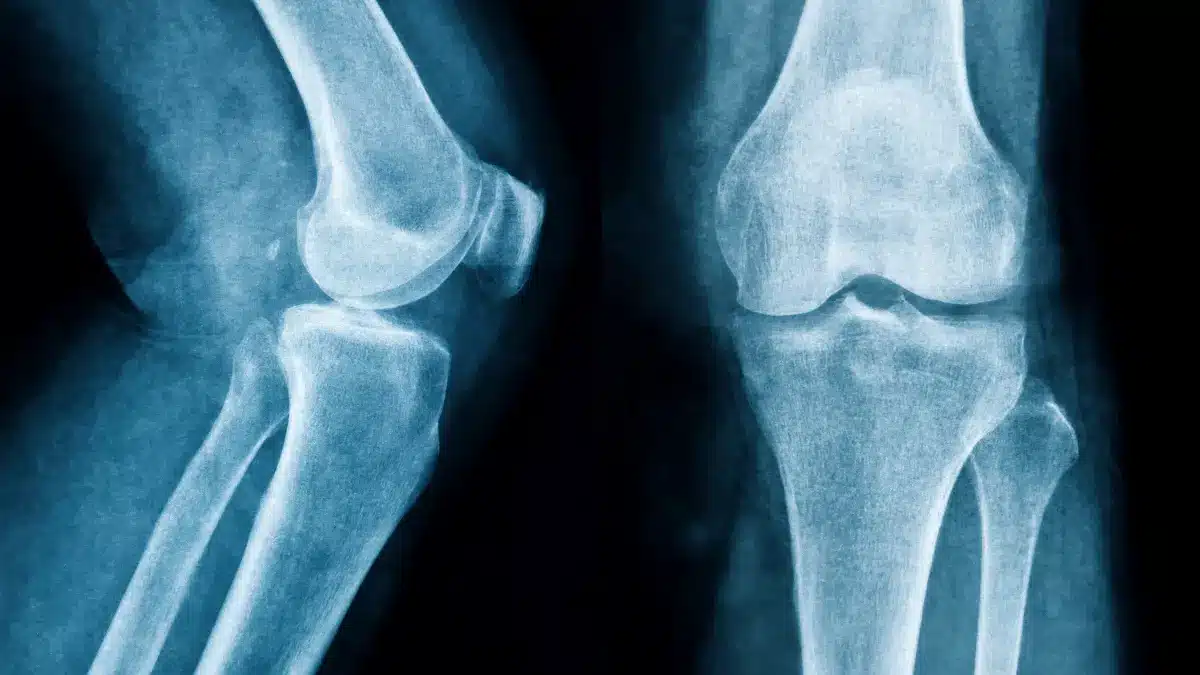

Lesões e Doenças do Joelho

Sintomas de joelho quebrado: veja sinais e cuidadosO joelho pode ser afetado por fraturas em diferentes ossos, como patela, tíbia e fêmur. Acidentes de trânsito, quedas e… Leia mais »